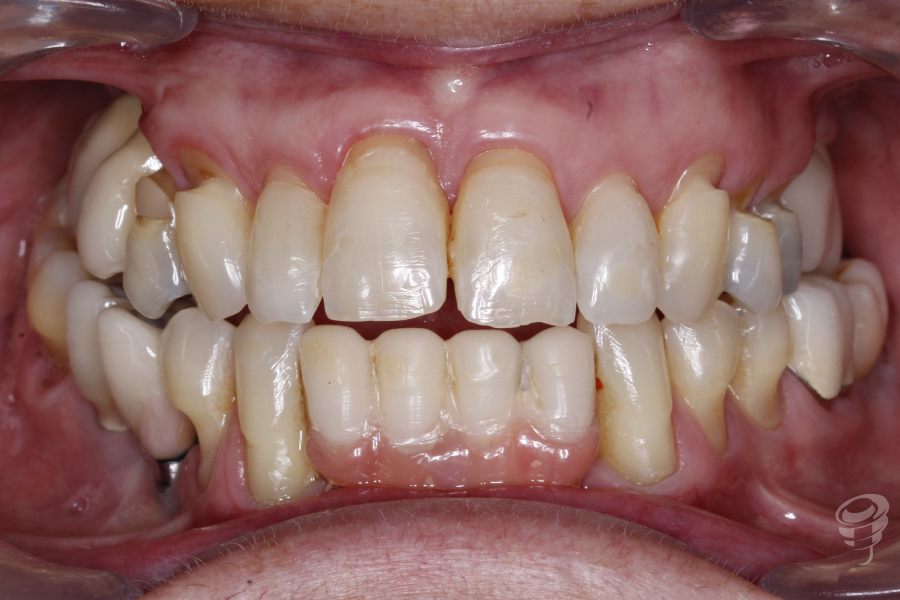

Podemos notar la pérdida de soporte periodontal que hay en el 11 y 21 y una descompensación asimétrica de los márgenes gingivales. Además, mordida abierta anterior y posterior derecha, mordida cruzada posterior bilateral, guías caninas ausentes. Un precario ajuste oclusal y bruxista. Podemos observar notables signos de abfracción en los cuellos 14, 13, 23, 24 y 25.

Figura 1

Figura 2

Figura 3

Figura 4